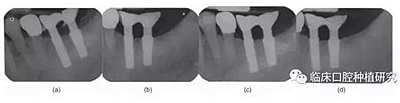

早期Albrektsson等(1986)提出的成功標準為種植體負載第一年邊緣骨吸收改變<1-1.5 mm,且隨后每年的骨吸收<0.2 mm。有學者發(fā)現(xiàn),種植體負載12個月以后邊緣骨吸收量與種植系統(tǒng)光滑表面的長度相關,因此將骨吸收和“第一螺紋”水平聯(lián)系在一起。(Jung et al. 1996)。1999年Hansson等首先提出種植體頸部微螺紋結構有助于獲得初期穩(wěn)定性和減少邊緣骨吸收。

本研究的目的是評估種植體MicrothreadTM微螺紋結構對維持種植體周邊緣骨水平的長期效果的作用。通過對同一種植系統(tǒng)(Astra)的兩種種植體(Astra Tech Single Tooth:帶頸部微螺紋和AstraTech TiOblast:不帶微螺紋)的三年前瞻性觀察研究,發(fā)現(xiàn)頸部微螺紋設計有助于維持種植體邊緣骨水平穩(wěn)定。

但是MicrothreadTM微螺紋設計對牙槽骨水平的早期穩(wěn)定性的效果仍待證實。針對骨的機械性能的研究(Guo 2001)發(fā)現(xiàn)骨組織對壓應力的抵抗力最強,對牽張應力的抵抗強度減少30%,對側向剪切力的抵抗力則減少65%。因此為了將骨吸收量降至最低,可以減少牙槽骨側向剪切力的種植體頸部設計是非常重要的。需要進一步有關微螺紋和種植體其他設計元素的研究來明確種植體設計和牙槽骨吸收的關系和機制。